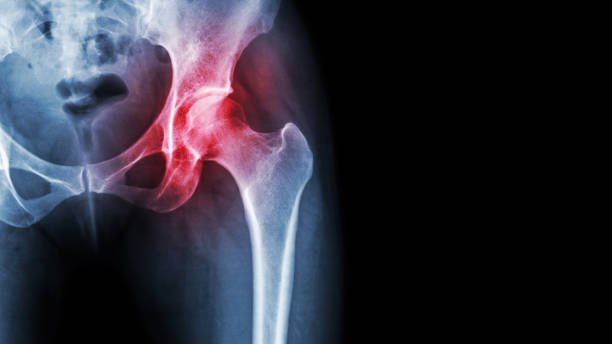

Rheumatoid arthritis (RA) is a chronic inflammatory disorder that primarily affects the joints, but it

also impact other systems in the body, including the skin, eyes, heart, lungs, and blood vessels. Unlike

wear-and-tear damage of osteoarthritis, RA affects the lining of your joints, causing painful swelling

can eventually result in bone erosion and joint deformity.

- Imaging Studies: X-rays, ultrasound, and MRI scans to assess joint damage and

inflammation.